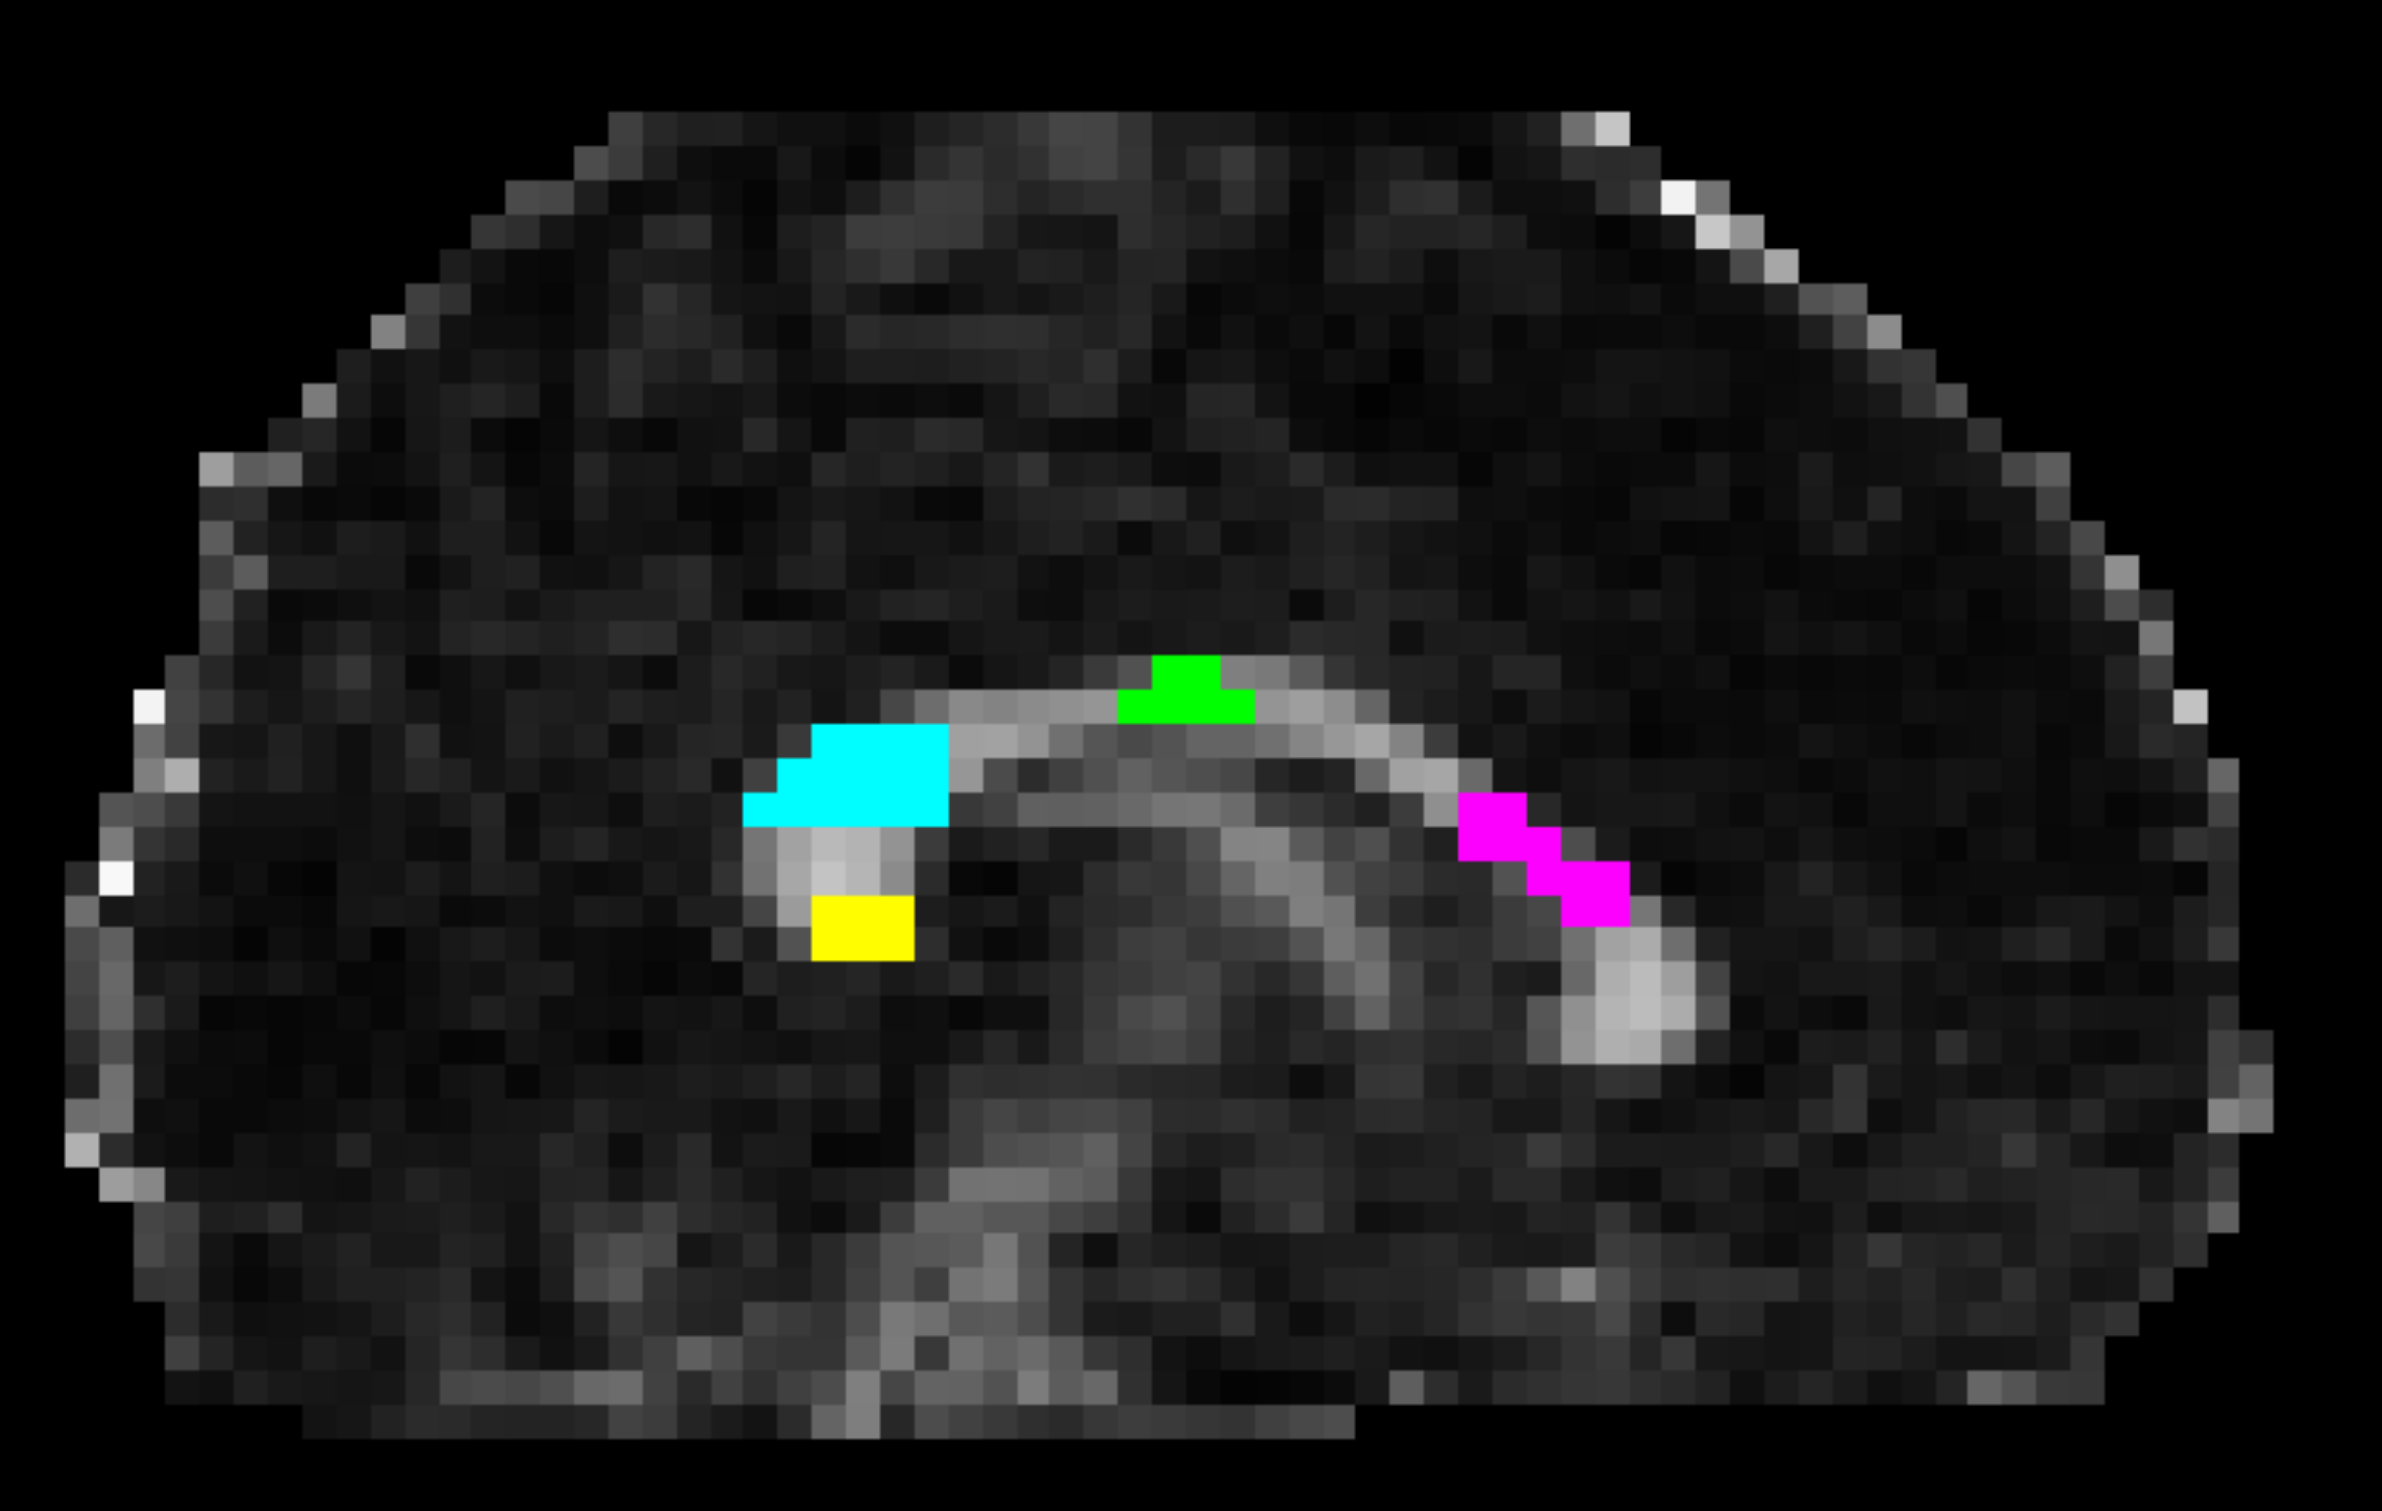

In vivo data acquisition and analysis: 6 healthy volunteers were scanned on a Connectom scanner (300 mT/m gradients) with a 20-channel RF coil. The study was approved by the ethics committee and all participants provided written informed consent. We used a diffusion-relaxation protocol8 simultaneously varying TE=[63,85,130,85]ms, b-tensor-shapes=[1,1,1,0.5] and b-values=[0,100,1000,2000,5000] s/mm2 with a 2.5 mm isotropic resolution. T2 values were estimated by means of a two-compartment model represented by a “stick” (intra-axonal) and a “zeppelin” (extra-axonal)8. For each dataset, four Regions of Interest (ROI) were manually drawn on the Corpus Callosum (CC) using fslview9 matching the CC sectors of the histology samples (see Figure 1). Intra-axonal T2values were extracted from the maps according to the ROIs, and the computed means were used in the correlation analysis.

Figure 1. Corpus Callosum ROIs example in a representative subject. The ROIs were manually drawn on multiple slices of the FA map to enhance the contrast and were based on the regions matching the histology sample. From right to left: ROI2 in pink; ROI5 in green; ROI8 in light-blue; ROI10 in yellow.